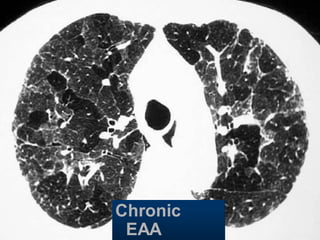

Chronic

EAA

Hypersensitivity pneumonitis

Extr. Allerg. Alveolitis (EAA) HRCT

Morphology

acute - subacute

acinar (centrilobular) unsharp densities

ground glass (patchy - diffuse)

chronic: fibrosis

Intra- / interlobular septal thickening

Irregular interfaces

Traction bronchiectasis